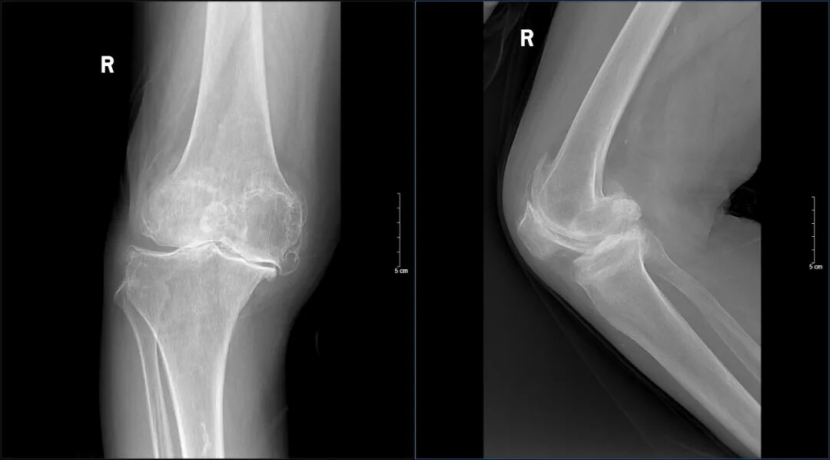

患者10余年前开始出现右膝关节疼痛,长期自行口服镇痛药,未接受系统规范治疗。病痛逐年加重。逐渐出现膝关节内翻畸形,活动受限明显,日常生活深受影响。为进一步治疗来到济南南郊医院骨科就诊。门诊检查后,以“双侧膝关节骨性关节病”收入院。

入院后,骨科杨学良主任团队为老人进行了详细查体及影像学评估。排除传统关节镜清理、单髁置换及截骨手术的适用性,确定全膝关节表面置换术为唯一根治方案。因患者术前心电图及心脏彩超异常,手术风险较高,团队启动多学科协作(MDT),联合心内科制定周密围手术期方案,待条件达标后如期手术。